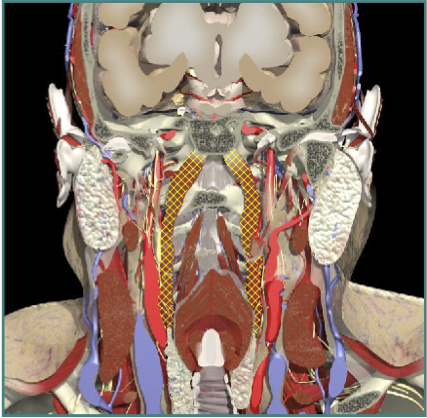

ACCURACY OF LOCALIZATION - SCALENES

ACCURACY OF LOCALIZATION LEVATOR SCAPULAE

LOCALIZATION OF MUSCLES IN DEEPER LAYERS

Layer 1

Layer 2

Layer 3

Splenius Capitis

Semispinalis Capitis

Longissimus Capitus

Semispinalis Cervicis

ACCURACY OF LOCALIZATION – DEEPER LAYERS